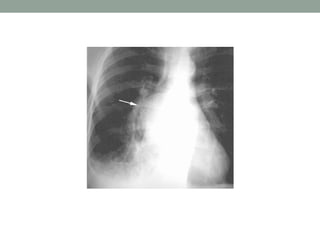

Right-sided aortic arch.

Posteroanterior chest

radiograph demonstrates an

abnormality in the right

paratracheal region (arrow) with

loss of the paratracheal stripe.

Note, however, the absence of

the aortic knuckle on the left.

• A right-sidedaortic arch, seen in 0.5% of the general population , may mimic paratracheal lymphadenopathy because it obliterates the right paratracheal stripe; however, the absence of the aortic knuckle on the left should help correctly identify this variant.

Right-sided aortic arch. Posteroanteriorchest radiograph demonstrates an abnormality in the right paratracheal region (arrow) with loss of the paratracheal stripe. Note, however, the absence of the aortic knuckle on the left.